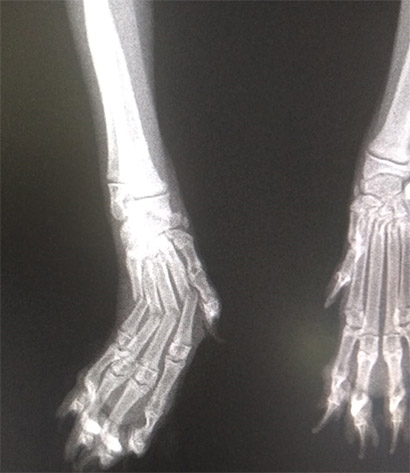

Die Röntgenuntersuchung brachte dann das Ergebnis: Maya hat vier gebrochene Zehen, eine OP ist absolut notwendig.

Klein-Maya wurde jetzt operiert.

Es wurde kein Draht, sondern ein Implantat in die Pfote gesetzt, damit die Knochen wieder korrekt zusammen wachsen können.